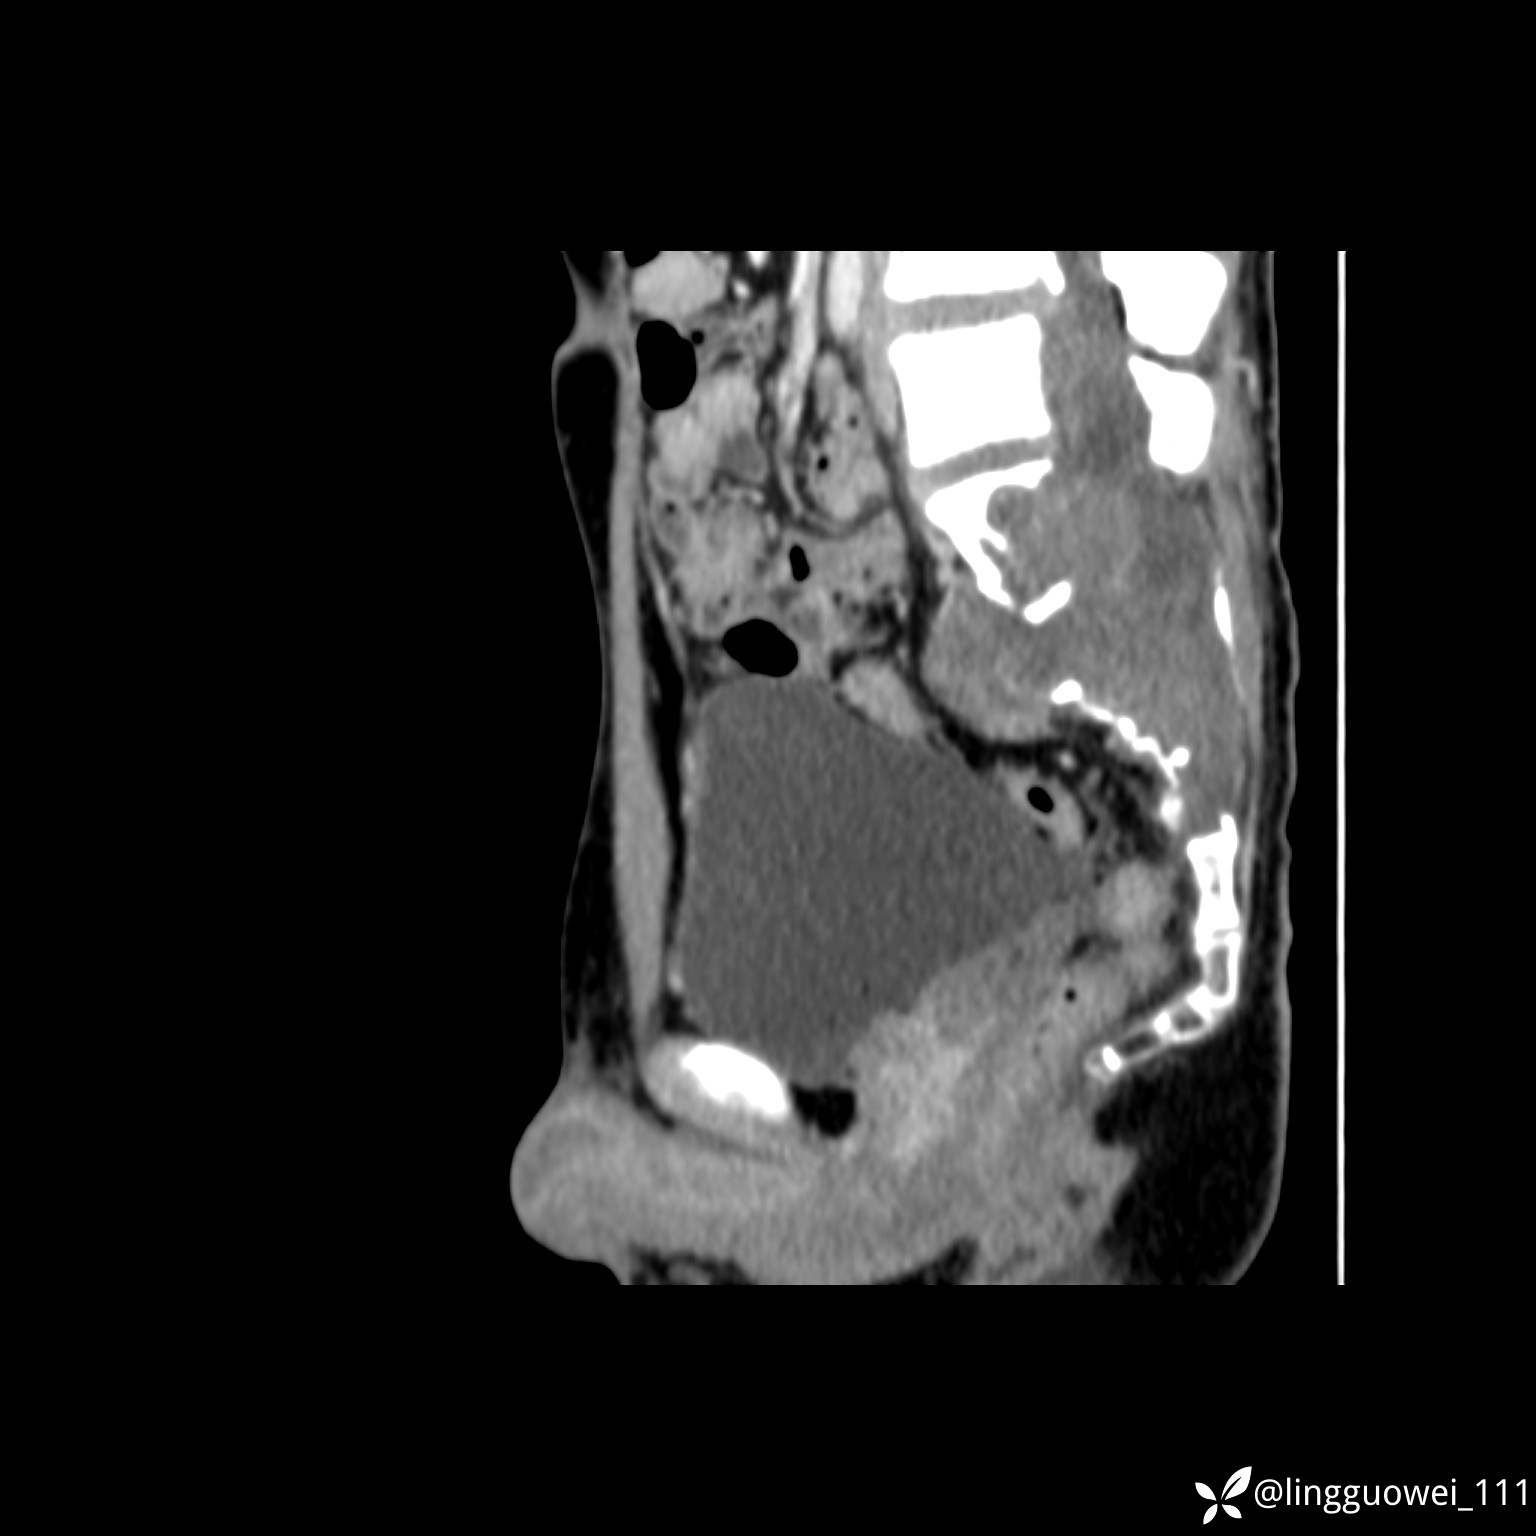

img